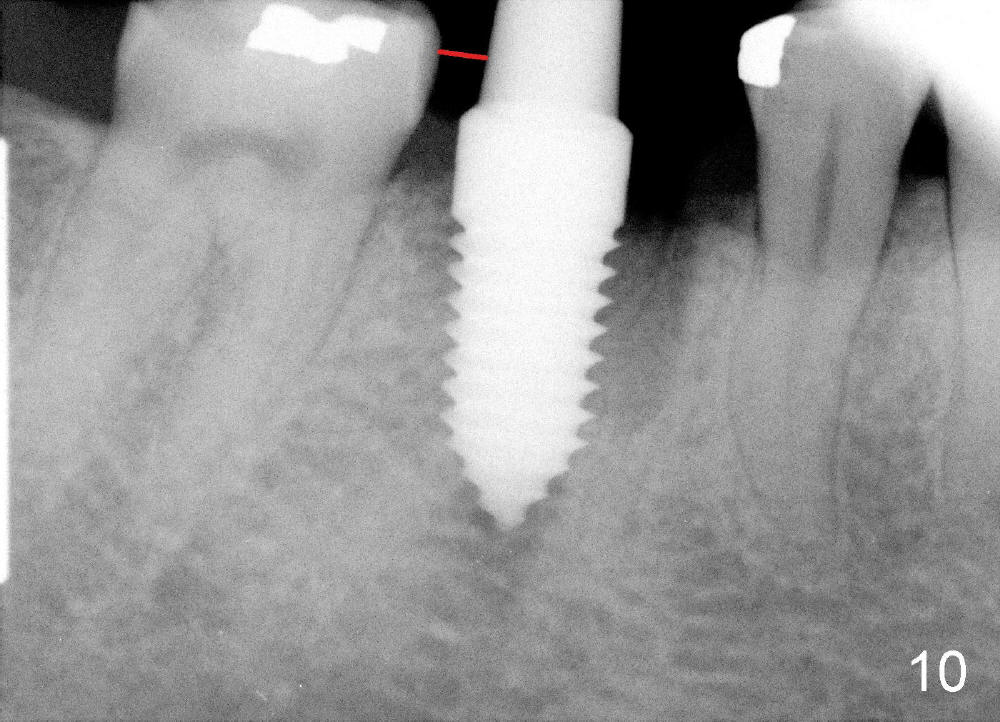

A 38-year-old lady agrees to have implant placement 7 years after loss of the crown of the lower right first molar (Fig.1,2). When the tooth is extracted, the septum is found to be low (Fig.3,4). To confirm it, a PA is taken (Fig.5). To initiate an osteotomy in the septum, it is trans-sectioned with thin osteotomes as shown in Fig.4 insert (black line). A 2 mm pilot drill is placed in the septum (Fig.6: P). The osteotomy is enlarged by 2.5-4.0 mm reamers (Fig.7,8), followed by insertion of 6x17 mm tapered tap at the depth 14 mm (Fig.9). The osteotomy is further enlarged by 4.5 and 5.0 mm reamers. A 6.0x14 mm one piece implant is placed initially. The trajectory is not ideal. A 6.0x14 mm one piece implant is placed initially. The trajectory is not ideal. The implant is removed from the osteotomy partially and reinserted with improved trajectory (Fig.11, compare to Fig.10 (red line)). Primary stability is high. There is not much bone mesiodistally so that the trajectory is easily changed in that direction. After abutment preparation, mixture of autogenous bone (harvested from reamers) and allograft is placed in the residual mesial and distal sockets (Fig.12). To contain the bone graft, an immediate provisional is placed (Fig.13 P). The occlusal plane of the provisional is significantly lower than that of the adjacent teeth to avoid micromovement of the implant. The patient is advised to eat soft food on the left side. Six days postop, the patient returns for prophy. The provisional is removed; the bone graft appears to be incorporating into the socket (Fig.14). After recementation, the provisional remains in place for 3.5 months; PA shows increased bone density in the mesial and distal sockets (Fig.15, compare to Fig.5,11). Due to insurance coverage, the patient defers fabrication of definitive restoration for at least 7 months. The immediate provisional is finally lost 8.5 months postop: the gingiva attaches to the 1-piece implant (Fig.16), while the density of the mesial socket increases (Fig.17 *) with formation of the cortex (lamina dura) coronally (v). Before the provisional (Fig.18 P) is removed for cementation of the definitive restoration, black shadow (*) is noted over the buccal gingiva. It is partially due to buccal placement (Fig.19) and partially due to buccal atrophy over a period of 10.5 months postop. How to prevent buccal placement? Positioning the first pilot drill in the septum buccolingually is a key. Eleven months post crown (Fig.20 C) cementation, the black shadow remains, but there is no tenderness. If the implant threads are immediately underneath the periosteum, there is tenderness.